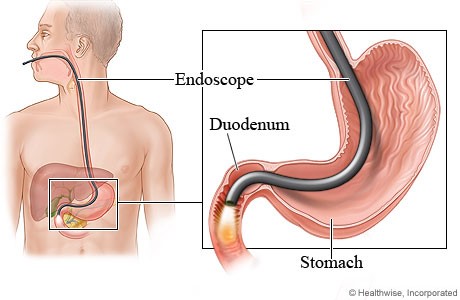

❈ What is upper endoscopy?

Upper endoscopy lets your doctor examine the lining of the upper part of your gastrointestinal tract, which includes the esophagus, stomach and duodenum (the first portion of the small intestine). Your doctor will use a thin, flexible tube called an endoscope, which has its own lens and light sou e, and will view the images on a video monitor.

❈ Why is upper endoscopy done?

Upper endoscopy helps your doctor evaluate symptoms of upper abdominal pain, nausea, vomiting or difficulty swallowing. It’s the best test for finding the cause of bleeding from the upper gastrointestinal tract. It is also more accurate than X-ray films for detecting inflammation, ultumoursnd tumors of the esophagus, stomach and duodenum. Your doctor might use upper endoscopy to obtain a biopsy (small tissue samples). A biopsy helps your doctor distinguish between benign (noncancerous) and malignant (cancerous) tissues. Remember, biopsies are taken for many reasons, and your doctor may take a biopsy even if he or she does not suspect cancer. For example, your doctor might use a biopsy to test for Helicobacter pylori, the bacterium that causes ulcers. Your doctor might also use upper endoscopy to perform a cytology test, where he or she will introduce a small brush to collect cells for analysis. Upper endoscopy is also used to treat conditions of the upper gastrointestinal tract. Your doctor can pass instruments through the endoscope to directly treat many abnormalities – this will cause you little or no discomfort. For example, your doctor might stretch (dilate) a narrowed area, remove polyps (usually benign growths) or treat bleeding.

What happens during upper endoscopy? Your doctor might start by spraying your throat with a local anesthetic or by giving you a sedative to help you relax.

You’ll then lie on your side, and your doctor will pass the endoscope through your mouth and into the esophagus, stomach and duodenum. The endoscope doesn’t interfere with your breathing. Most patients consider the test only slightly uncomfortable, and many patients fall asleep during the procedure.